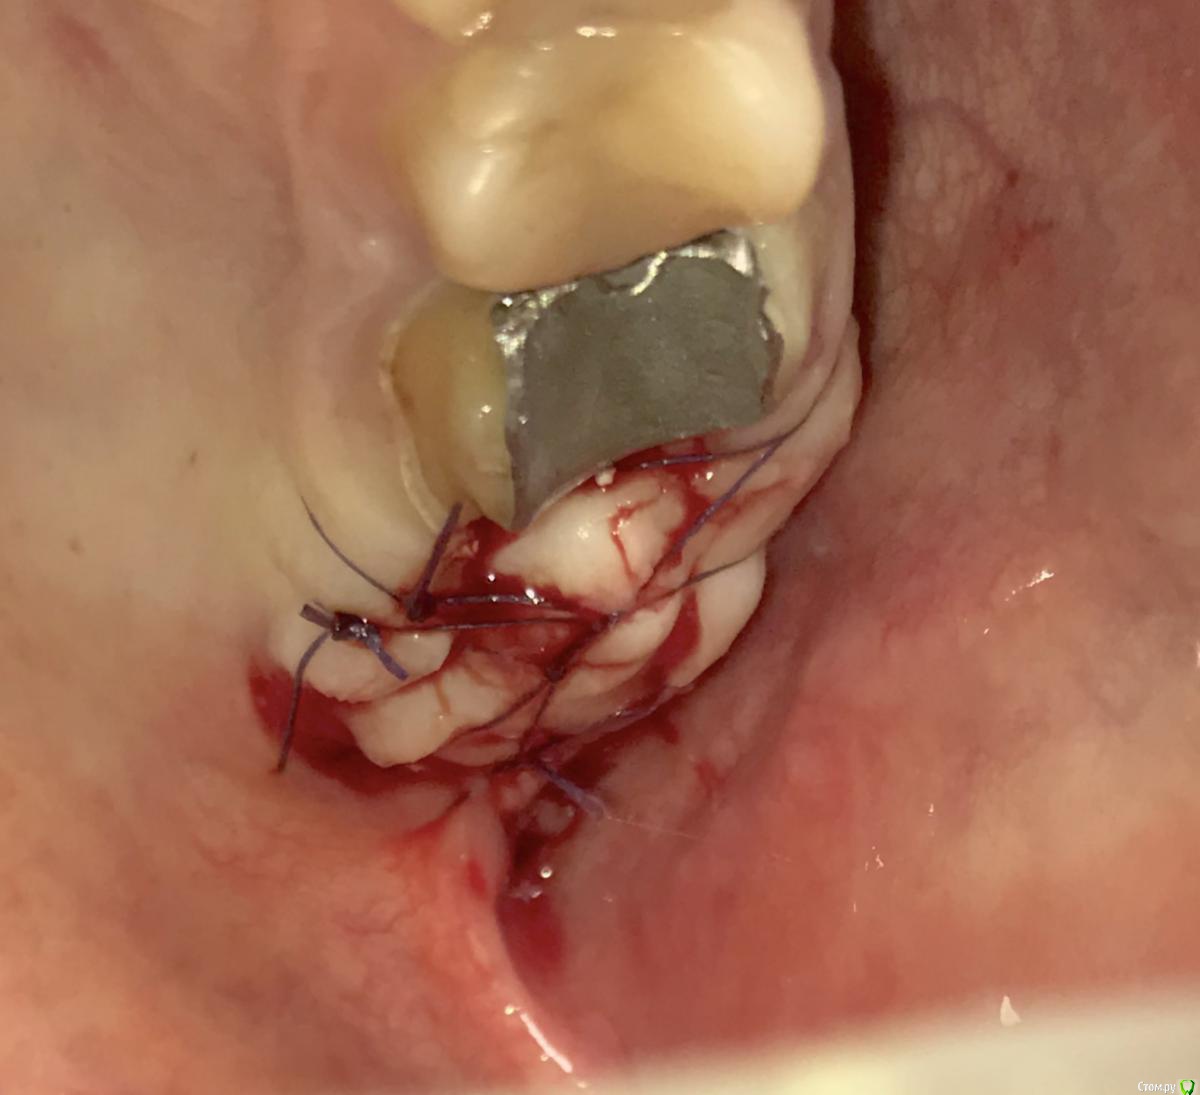

колесников Опубликовано 9 мая, 2017 Автор Поделиться Опубликовано 9 мая, 2017 Да,"приберечь " это про низ. Бугор берётся расщеплённый,не полностью, хорошо регенерирует . Через 4 недели можно брать снова. Травма у нас местно есть в любом случае,кератинизированая расщеплённая десна регенерирует очень хорошо и малоболезненно. Как пример фото разместил :в первом случае со "змейки " я снял швы через неделю и простился,во втором ,где свободный лоскут,остатки его убрал через 3 недели и ещё неделя наблюдений.На фото расщеплённый бугор. На последнем -с выделенным сст. Ссылка на комментарий

колесников Опубликовано 5 июля, 2019 Автор Поделиться Опубликовано 5 июля, 2019 Ещё раз о ретировалось лоскуте . Из ретромолярной зоны на н/ч перекинут Вестибулярно к 7ке и с неба перекинут Вестибулярно уже для верхней 7ки. Оба случая значительный дефект вестибулярной стенки,одномоментная имплантация,грануляции. Получается хороший стабильный и плотный каркас. 1 зона. 1 Ссылка на комментарий